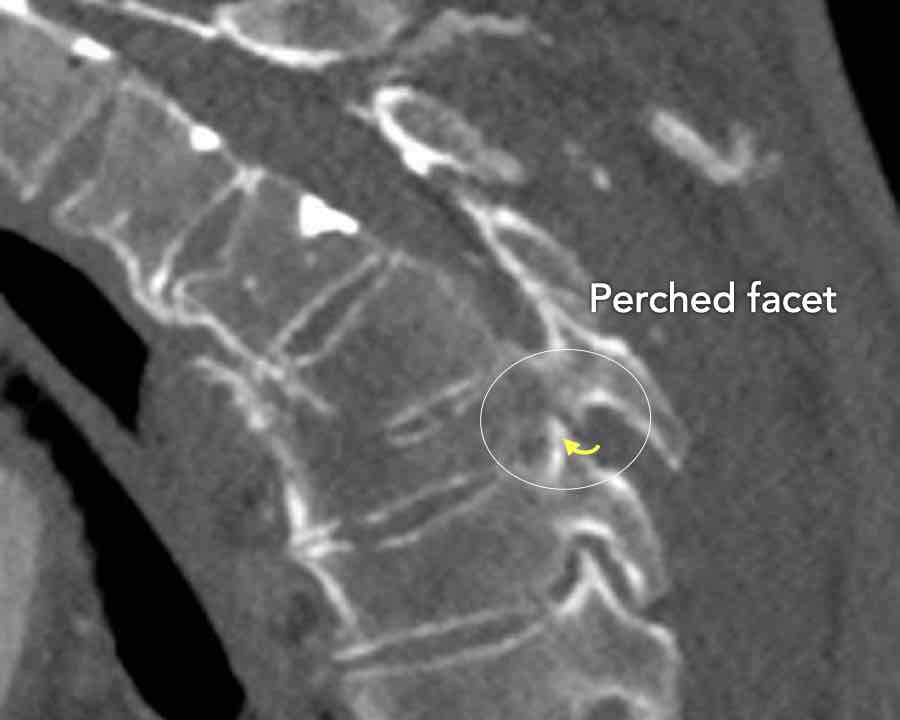

Scroll through the images

Findings:

- Perched facet joints (yellow curved arrows), so think of C injury.

- Posterior displacement of the vertebral bodies in the midline.

- Secondary A4 injury of the vertebral body.

Conclusion

Type C + A4 injury